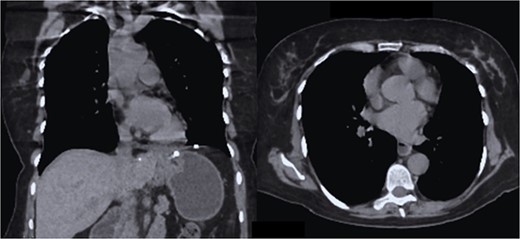

The patient had 2 days of post-surgical hospital surveillance with early mobilization, was discharged on the second day with tolerance to a liquid diet, and was followed up in the outpatient clinic at 7 days, 3 months, and 6 months with imaging studies in which both lung fields re-expanded without the presence of recurrences (Fig. 7), and reported total remission of symptoms.

CT coronal and axial sections, showing complete re-expansion of both lung fields and the fixed mesh at the level of the hiatus esophageal without evidence of a hernia sac or recurrence.